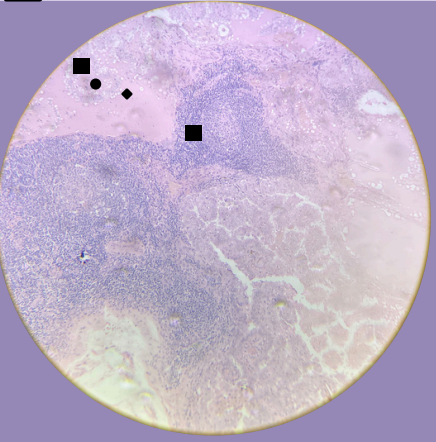

Seminoma:

Estroma escaso y fibroso

Células tumorales forman masas sólidas

Citoplasma claro